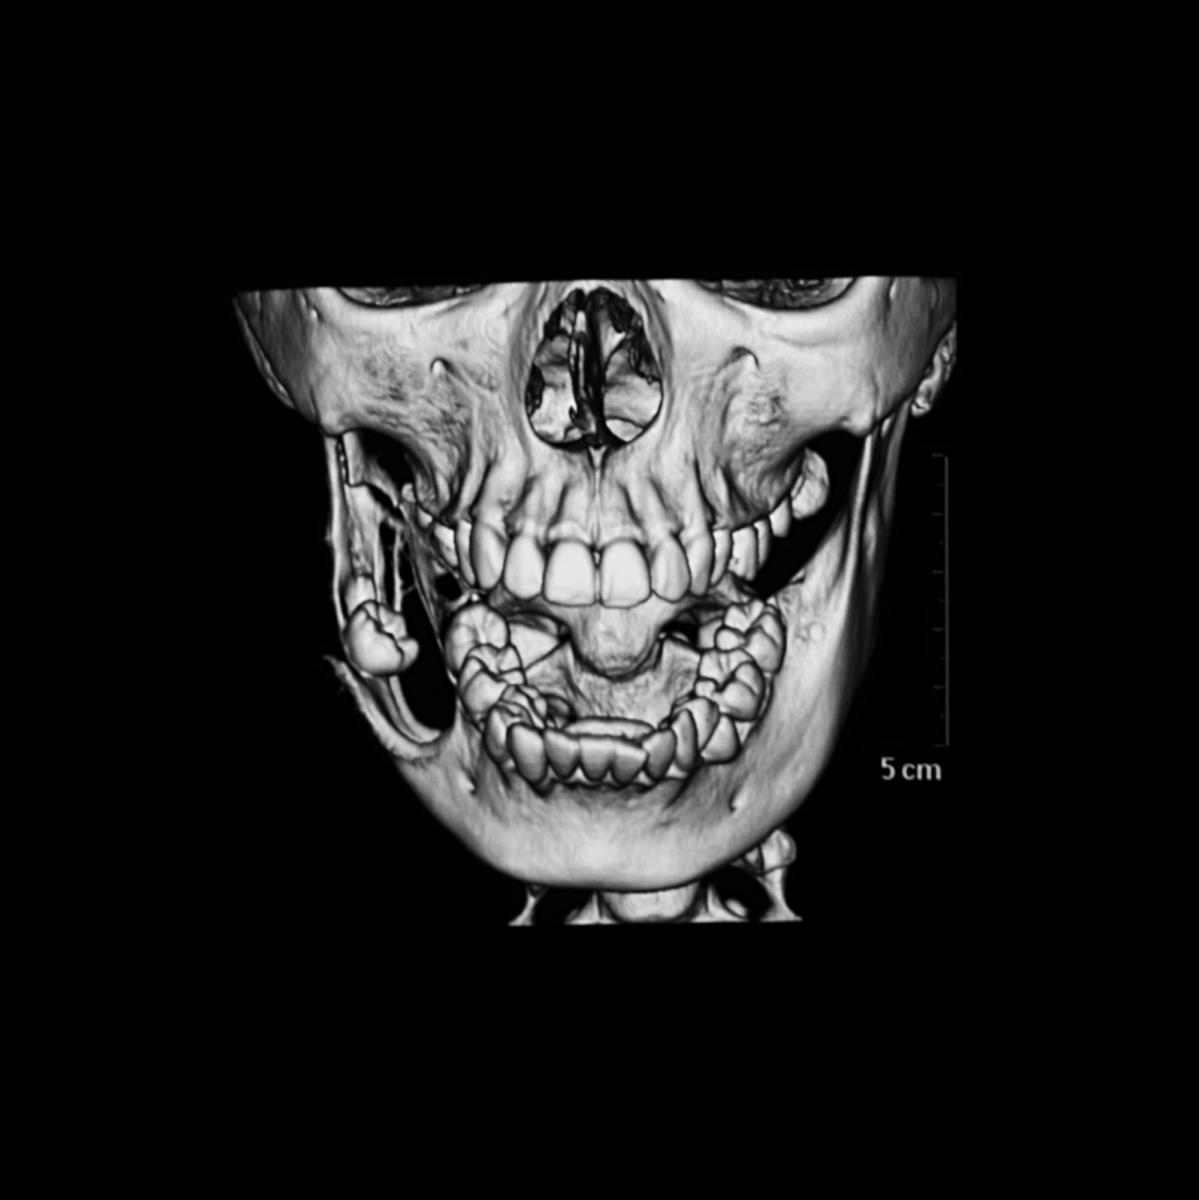

L'examen clinique et radiographique

Lors de l’examen clinique, le médecin examinera attentivement la zone affectée pour déterminer si elle est enflée ou sensible au toucher. Il peut également prescrire une radiographie panoramique pour obtenir une vue complète du crâne et de la mâchoire afin de confirmer le diagnostic.